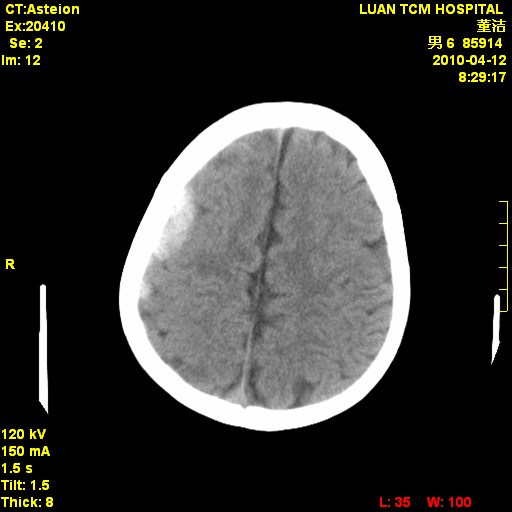

标题: PED3404:有结果,先猜猜这是啥病表现?男,12岁。 [打印本页]

标题: PED3404:有结果,先猜猜这是啥病表现?男,12岁。

右侧额顶部自颅板向内近似半圆高密度影,周围无明显水肿,考虑:脑外血肿?脑膜瘤?淋巴瘤?